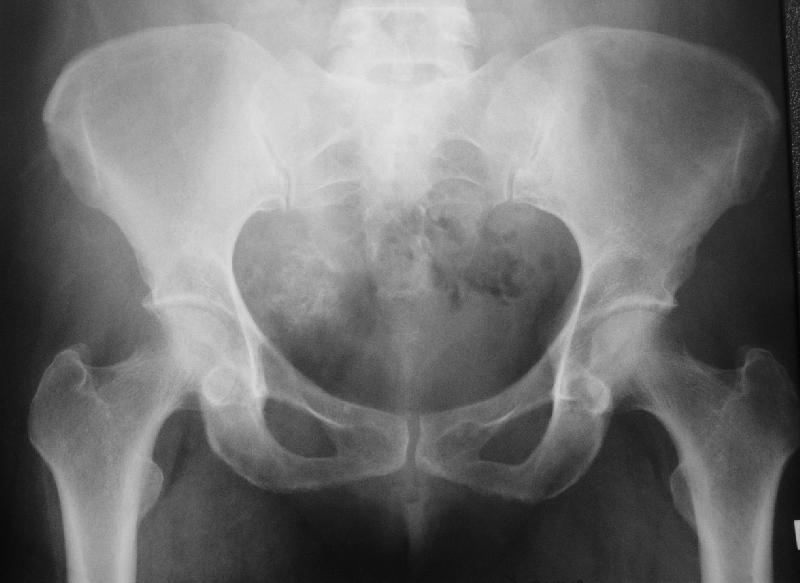

Хондрома таза

Больная 53 лет обратилась с жалобами на боли в левом паху, отдающие в левое бедро и стопу, которые появились около года назад, затруднения при дефекации.

В марте 2003 года лапаротомия по поводу предпологаемого дивертикулеза толстой кишки, обнаружили опухоль. В апреле биопсия подвздошным доступом DS - Хондрома таза. Вопросы: Объем операции, доступ, где можно сделать, сколько может стоить?